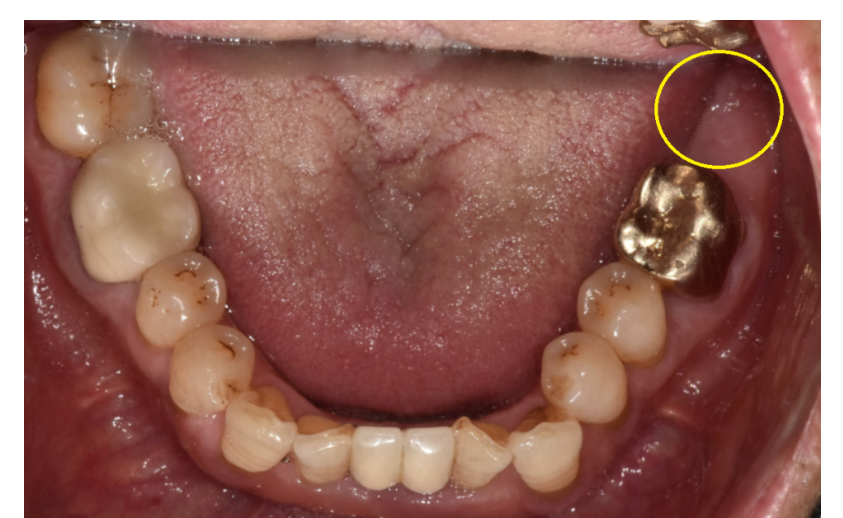

구강 내 사진을 촬영하고

구강 내 사진 및 잇몸 상태 검사